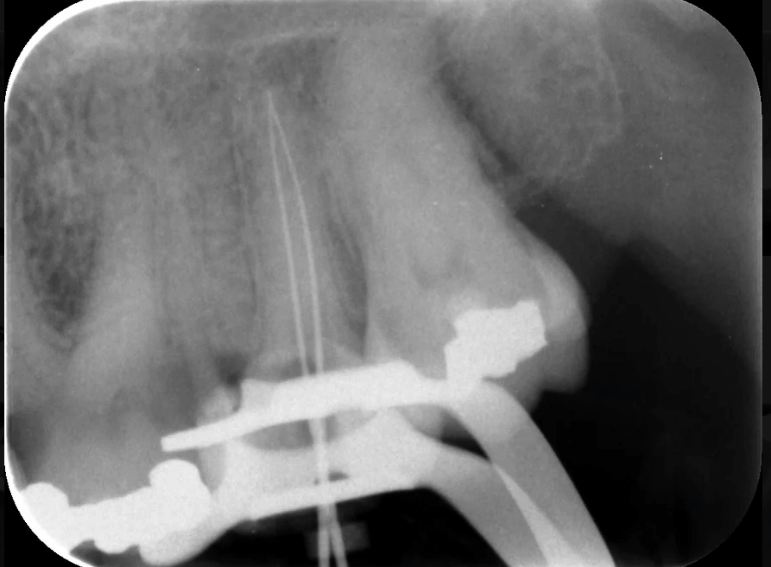

Root filling of a molar tooth.